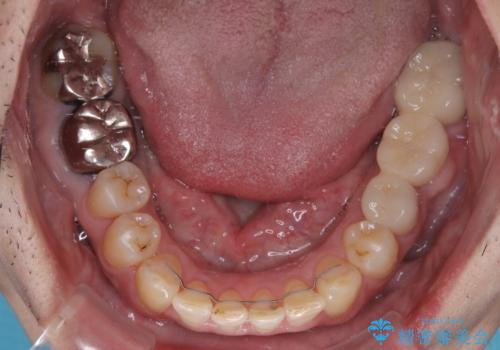

- 近医にてブリッジ治療を行った歯が痛くてたまらないとのことで来院された患者様です。

診察を行ったところ、奥の土台になっている歯は神経組織が失活しており、根尖部に病変があり、そこが原因で痛みを生じている状態でした。

根管治療を行うためにブリッジを除去したところ、むし歯が歯肉の奥深くにあまで及んでいたため、歯周外科処置によりむし歯が歯肉縁より浅い位置へと改善することとしました。

ここまでの治療を提案したところで、折角なのでしっかり治療を行いたいとのことで、前歯のデコボコやクロスバイトを改善するための矯正治療を行うこととしました。

まずは奥歯の痛みを改善し、その後矯正治療を行い、最後にオールセラミックブリッジによる補綴治療を行うこととしました。

むし歯をきっかけに矯正治療を行うこととなりましたが、学生の頃から気になっていた歯列を改善することができ、患者様には大変満足していただけました。